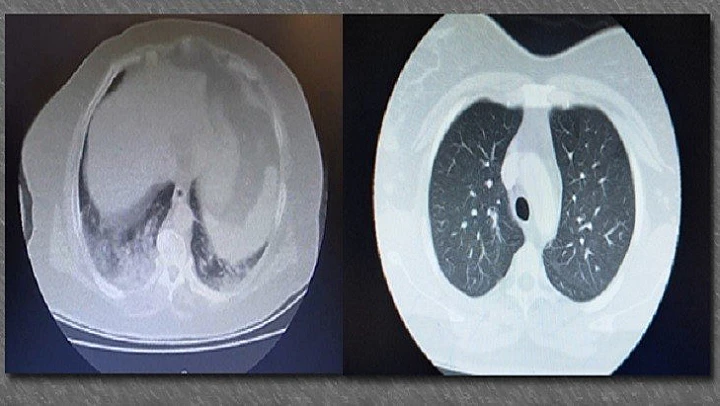

Edirne'de korona virüs salgınına yakalanan hastaları hayata döndürmek için özveriyle çalışan sağlık çalışanlarından biri olan Edirne Sultan 1. Murat Devlet Hastanesi Enfeksiyon Hastalıkları ve Klinik Mikrobiyoloji Uzmanı Dr. Alper Eker, korona virüs hastalığına yakalanan bir hastanın ciğerleriyle, sağlıklı bir kişinin ciğerlerinin karşılaştırıldığı tomografi görüntülerini İhlas Haber Ajansı (İHA) ile paylaştı.

Korona virüs hastalığına yakalanan ve hastanede tedavisi devam eden 65 yaşındaki bir vatandaşın, her iki akciğerindeki dokuların tamamen virüsle kaplandığı ve akciğer dokularının kaybolduğu tomografi görüntüsünü anlatan Dr. Eker, akciğerlerin kapasitesinin düşmesiyle birlikte hastanın solunum ve nefes darlığı sıkıntıları yaşamaya başladığını söyledi.